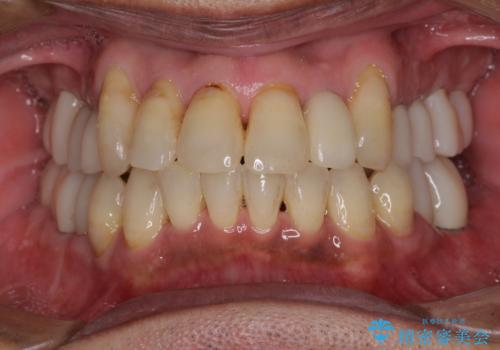

虫歯の進行などはさほど認められなかったので、根管治療実施後に速やかにオールセラミッククラウンにて補綴しました。

数年も前から気になっていた前歯が自然な仕上がりとなり、患者様には大変満足していただきました。